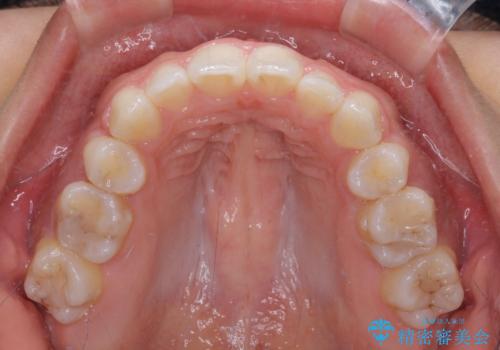

上顎抜歯のみでは奥歯の咬み合わせを改善することが困難であったため、途中で下顎小臼歯も抜歯をしました。

抜歯のタイミングが遅れると治療期間が長期化するため、速やかに抜歯の判断をし、2年強の期間で治療を終えることができました。